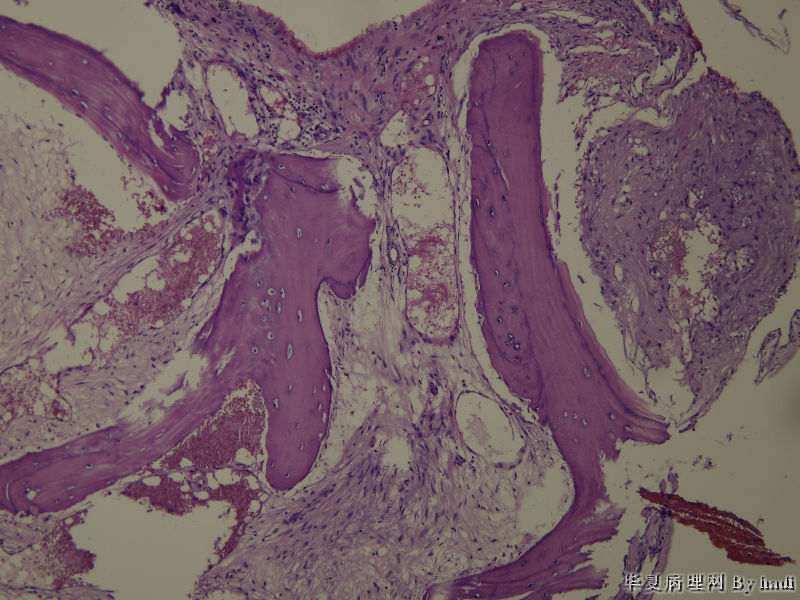

• 鼻腔肿瘤图4

图4